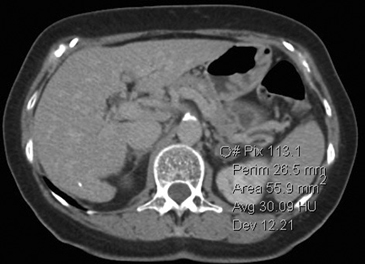

La presencia de lípidos intracelulares disminuye la densidad de la lesión debido a que estos son menos densos que el agua. El primer estudio en reportar la utilidad de la densitometría por TC en la diferenciación de una lesión suprarrenal benigna de una maligna fue el realizado por Lee et al6, utilizando la medición del coeficiente de atenuación o densidad de la lesión expresada en unidades Hounsfield (UH), en una TC no contrastada, demostrando que el coeficiente de atenuación promedio de los adenomas (2,2 UH) fue significativamente menor que la de las lesiones no adenomas (28,9 UH). Utilizando un punto de corte de 0 UH la sensibilidad de la TC no contrastada en la caracterización de un adenoma es cercana a un 47%, con una especificidad de aproximadamente 100% (Figura 9 a y b). Sin embargo, estudios posteriores7 han corroborado que al utilizar un punto de corte de 10 UH, la sensibilidad asciende a un 71%, y la especificidad se mantiene en prácticamente 98%, por lo que este umbral de densidad es el más utilizado en la actualidad. Es importante enfatizar que para una adecuada medición de la densidad, la región de interés (ROI) no debe incluir áreas de necrosis ni de hemorragia, y debe abarcar al menos la mitad o dos tercios de la lesión, para evitar el artefacto por ruido y el efecto de volumen parcial con el tejido adiposo adyacente (Figura 10).

A

B

Figura 10. Adenoma suprarrenal derecho. Lesión suprarrenal derecha, cuya densidad es consistente con un adenoma típico. En la imagen se demuestra una adecuada medición de la densidad lesional, con una región de interés (ROI) que abarca al menos dos tercios de ésta.